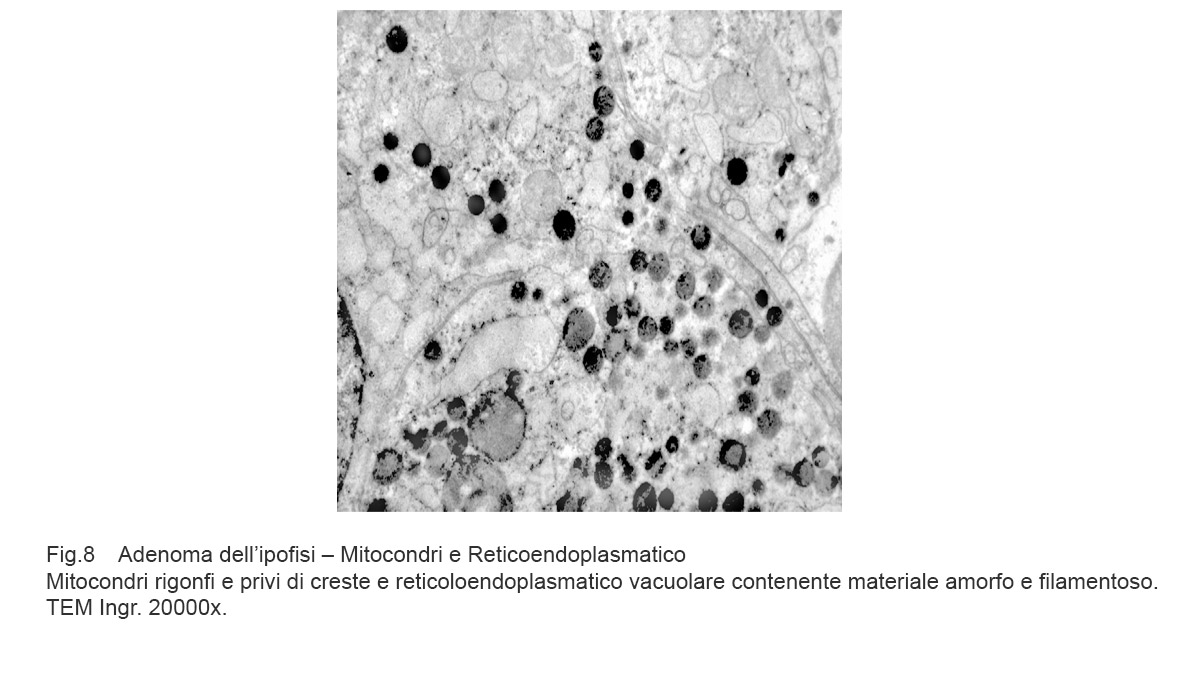

I dati rilevati possono essere sintetizzati nei seguenti punti descrittivi:

Mitocondri e R.E.: mitocondri rigonfi e privi di creste sono adiacenti ad ampia vacuolizzazione del reticolo endoplasmico; questi vacuoli sono frequentemente occupati da addensamenti di materiale amorfo e filamentoso(Reticoendoplasmatico in stato di stress).

Fig.7

Mitocondri e R.E. : mitocondri piccoli con una quota ridotta di creste sono incestellati da un reticolo endoplasmico che si snoda a rete con aspetto lacunare.(Reticoloendoplasmatico in stato di stress).

Fig.8